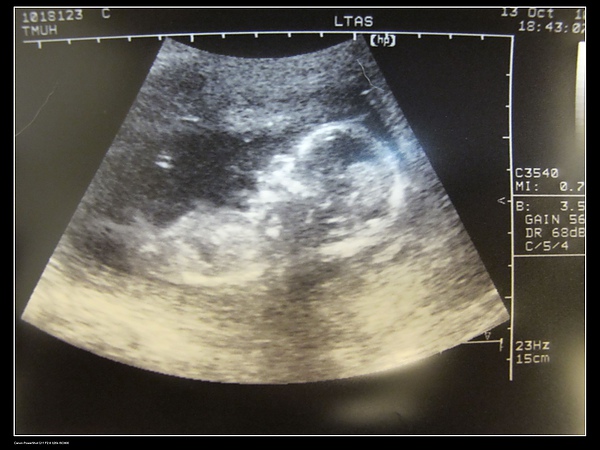

10.13

今天準備做16週的產檢,順便預約羊膜穿剌的日期

產檢最重要的項目是超音波,這樣我才能和我的小情人見到面

但在照超音波的時候,我發現超音波師的反應不太好